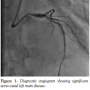

Before delivery of a 4.0 mm LM stent, another workhorse coronary wire was introduced into the guide and curled back into the aorta so that it now looked like the sepal of a flower and the guiding catheter like the flower stalk. The LM stent was then able to be advanced through the guiding catheter into the LM. At this stage, the guiding catheter was manipulated to situate closely to the ostium, but would be prevented from fully intubating into the LM by the “sepal” wire, and a more co-axial position

was thus achieved. This also allowed good contrast filling for visualization of the anatomical relationship (Figure 2). The 4.0 mm stent was deployed at 16 atmospheres (Figure 3). Final angiography showed excellent results (Figure 4), with the guiding catheter engaging easily into the LM after removal of the “sepal” wire. IVUS confirmed excellent ostial stent coverage (Figure 5).

Our novel technique is simple and easy to implement. The only additional device is a regular workhorse wire. This wire enables the guiding catheter to park closely to the true ostium, yet it cannot be intubated fully into the LM. It allows good contrast filling for visualization of the anatomical relationship and the wire itself also helps to demarcate the silhouette of the aortic sinus. Finally, precise adjustment of the stent’s position is made easy because the wire stops the guiding catheter from being “sucked” into the LM when one attempts to fine-tune the stent position by pulling the stent out to cover the true ostium. This technique is simple and safe and is very helpful for accurate ostial stent positioning. Finally, it is still of paramount importance to find good angiographic views to clearly show the anatomical relationship, which can be highly variable among individual patients. In our experience, right anterior oblique and left anterior oblique cranial projections are usually the best angles, as in this case. A final IVUS study helps confirm adequate stent expansion and apposition in addition to confirming the exact stent location.